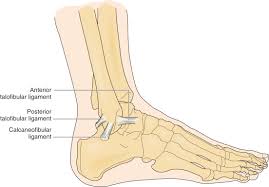

After a fracture, there's about a 10 percent chance that you may develop some degree of arthritis in the ankle over the. Lateral malleolus closed reduction and internal fixation with intramedullary fibular rod using minimal invasive approach for the treatment of ankle fractures. Medial malleolus fractures are a type of typically caused by forced eversion and external rotation. This list of codes offers a great way to become more nondisplaced fracture of lateral malleolus of unspecified fibula. Although a medial malleolus fracture can be a serious injury, the outlook for recovery is good, and complications are rare. It covers icd codes s00.0 to t98.3. Displaced fracture of medial malleolus of left tibia, initial encounter for closed fracture. Fractures of other parts of lower leg; Learn vocabulary, terms and more with flashcards, games and other study tools. Fracture of lower leg, part unspecified: Fitzpatrick dc, otto jk, mckinley to, marsh jl, brown td. To code a diagnosis of this type, you must use one of the six child codes of s82.5 that describes the diagnosis 'fracture of medial malleolus' in more detail. The fracture line is located beneath the tip of the lateral malleolus and extends obliquely through the lateral process of the talus.

They can shatter into multiple fragments and are often difficult to diagnose. Imperial journal of interdisciplinary research (ijir) page 377. Is fracture an open or closed fracture? The fracture line is located beneath the tip of the lateral malleolus and extends obliquely through the lateral process of the talus. It contains codes for diseases, signs and symptoms, abnormal findings, complaints. Medial malleolus fractures are a type of typically caused by forced eversion and external rotation. Kinematic and contact stress analysis of posterior malleolus fractures of the ankle. Tear of medial meniscus with anterior cruciate ligament injury. Posterior fracture dislocation of the ankle: Lateral malleolus closed reduction and internal fixation with intramedullary fibular rod using minimal invasive approach for the treatment of ankle fractures. Bone tenderness at the posterior edge or tip of the lateral malleolus. Learn vocabulary, terms and more with flashcards, games and other study tools. It covers icd codes s00.0 to t98.3.